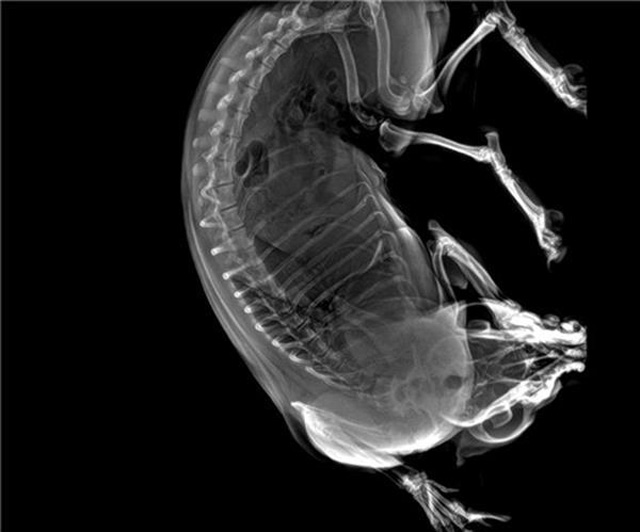

寵物DR的工作原理是X光線穿透動物體後在屏幕或者膠片上麵顯示體內影像。輔助寵物醫生讀片跟準確的治療,寵物DR顯示是寵物醫院診所的配置,提高了診斷的效率。DR的檢測效率比X線高44%,成像快采集時間10MS以下。3秒左右就可以看到檢查圖像。常規的胸部DR還要幾分鍾。所以寵物DR的出片速度是非常快的。很高的空間分辨率低噪音。可以獲得高清圖像,提高檢測正確率避免誤診等等問題。數字化圖像的優勢是可以保留原始數據,圖片識別,二三維的重建,醫學影像學實現全數字化和無膠片化鋪平了道路。提供照片打印服務,防止照片丟失而重複照片。有針對性的對圖像進行處理,以提高診斷率。寵物DR的輻射量很低的,對人體的輻射風險不大。